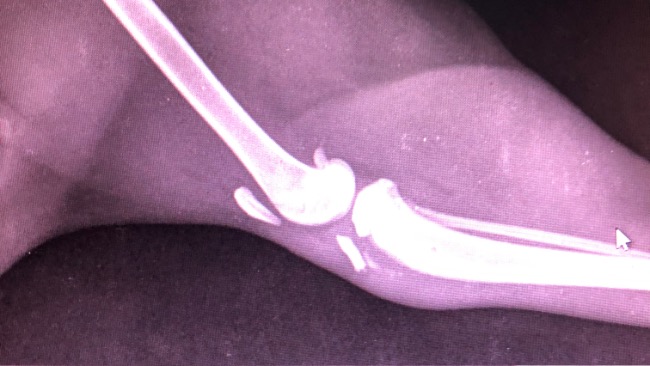

Niestety rtg wykazało oderwanie guzowatości piszczelowej w obrębie wzrostu kości 😭 Natychmiast potrzebna operacja !💔